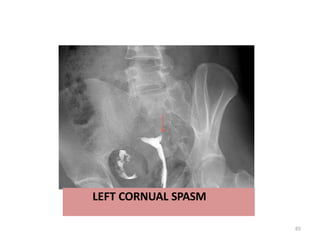

Cornual block presents with a history of

primary or secondary infertility. It may occur

due to nonspecific salpingitis following

abortion. Cornual spasm mimics cornual block

in hysterosalpingography. Approximately two-

thirds of the fallopian tubes resected for

cornual block reveal transient cornual spasm.

It is necessary to identify cornual block from

cornual spasm to avoid unnecessary

intervention.

LEFT CORNUAL SPASM